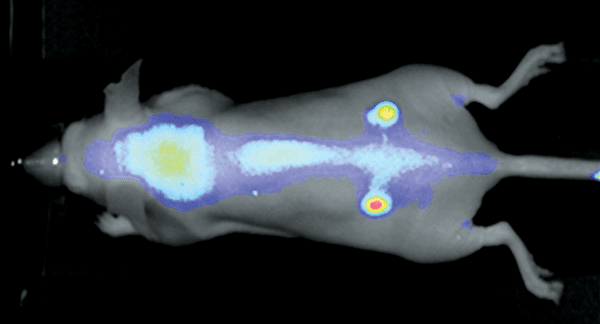

Figure 2. Nude mouse bearing subcutaneous tumors, U87 (left hip) and A431 (right hip), was imaged 24 h post intravenous injection of IRDye 800CW RGD (1 nmole). Image was captured on the Pearl Imager; 800 nm signal is presented in pseudo-color overlaid on a white light image of the mouse. Research conducted at LI-COR Biosciences.